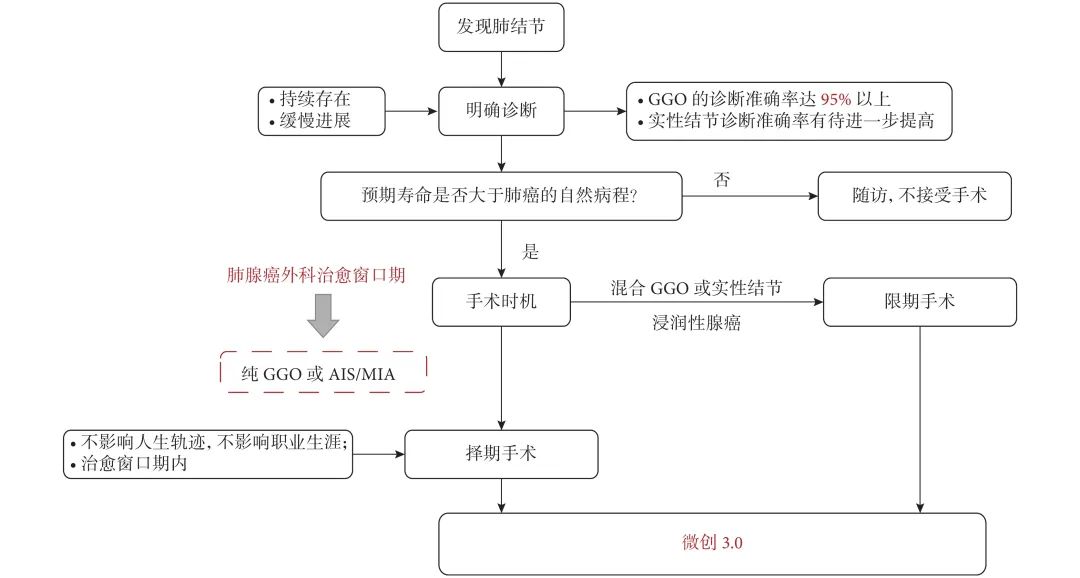

如何认识和理解肺腺癌外科治愈窗口期

如何认识和理解肺腺癌外科治愈窗口期